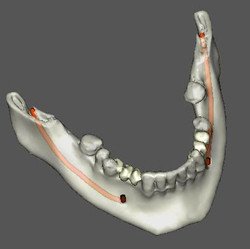

Caso 5: Dente retido

Dente 47 e 48 retidos, em posição mésio horizontal, sobrepostos com raízes superpostas ao canal mandibular. Ao exame tomográfico identifica-se o canal passando rechaçado entre os ápices do 48 e a cortical vestibular e passando entre as duas raízes mesiais do dente 47.